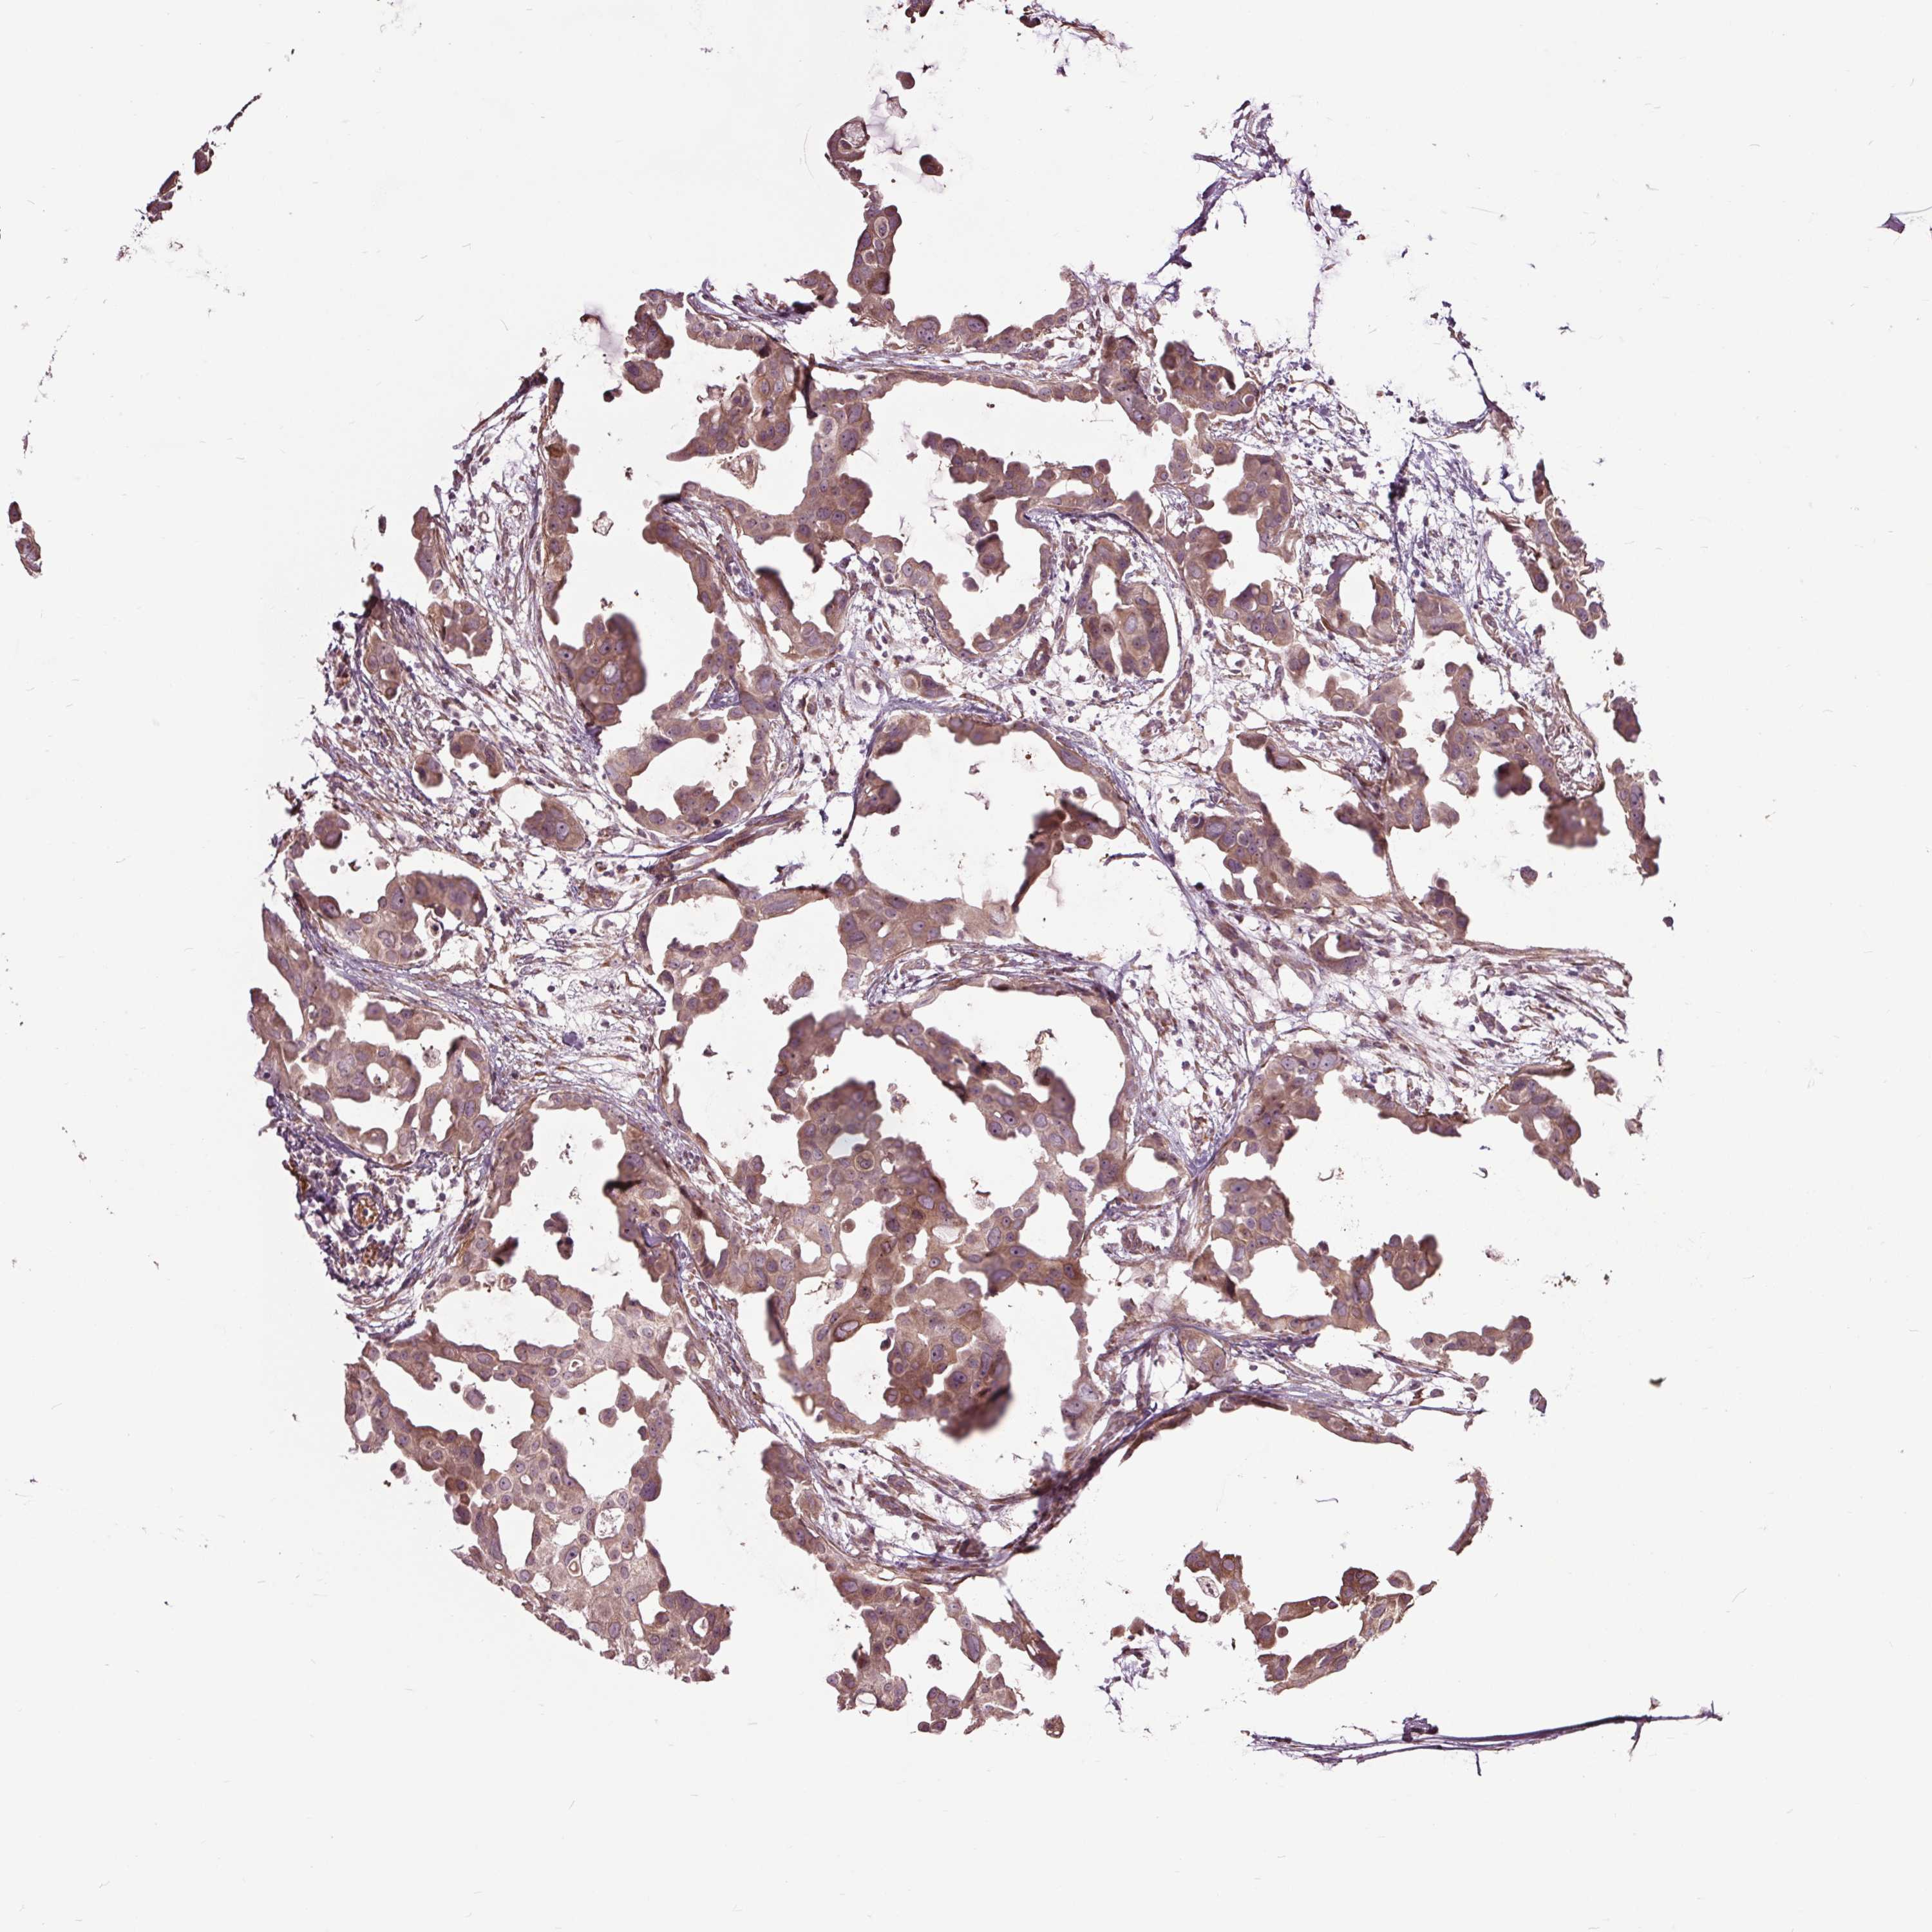

CANCER BREAST CANCER Show tissue menu

BRCA TCGA BRCA VALIDATION PROTEIN EXPRESSION

ANTIBODIES

AND

VALIDATION